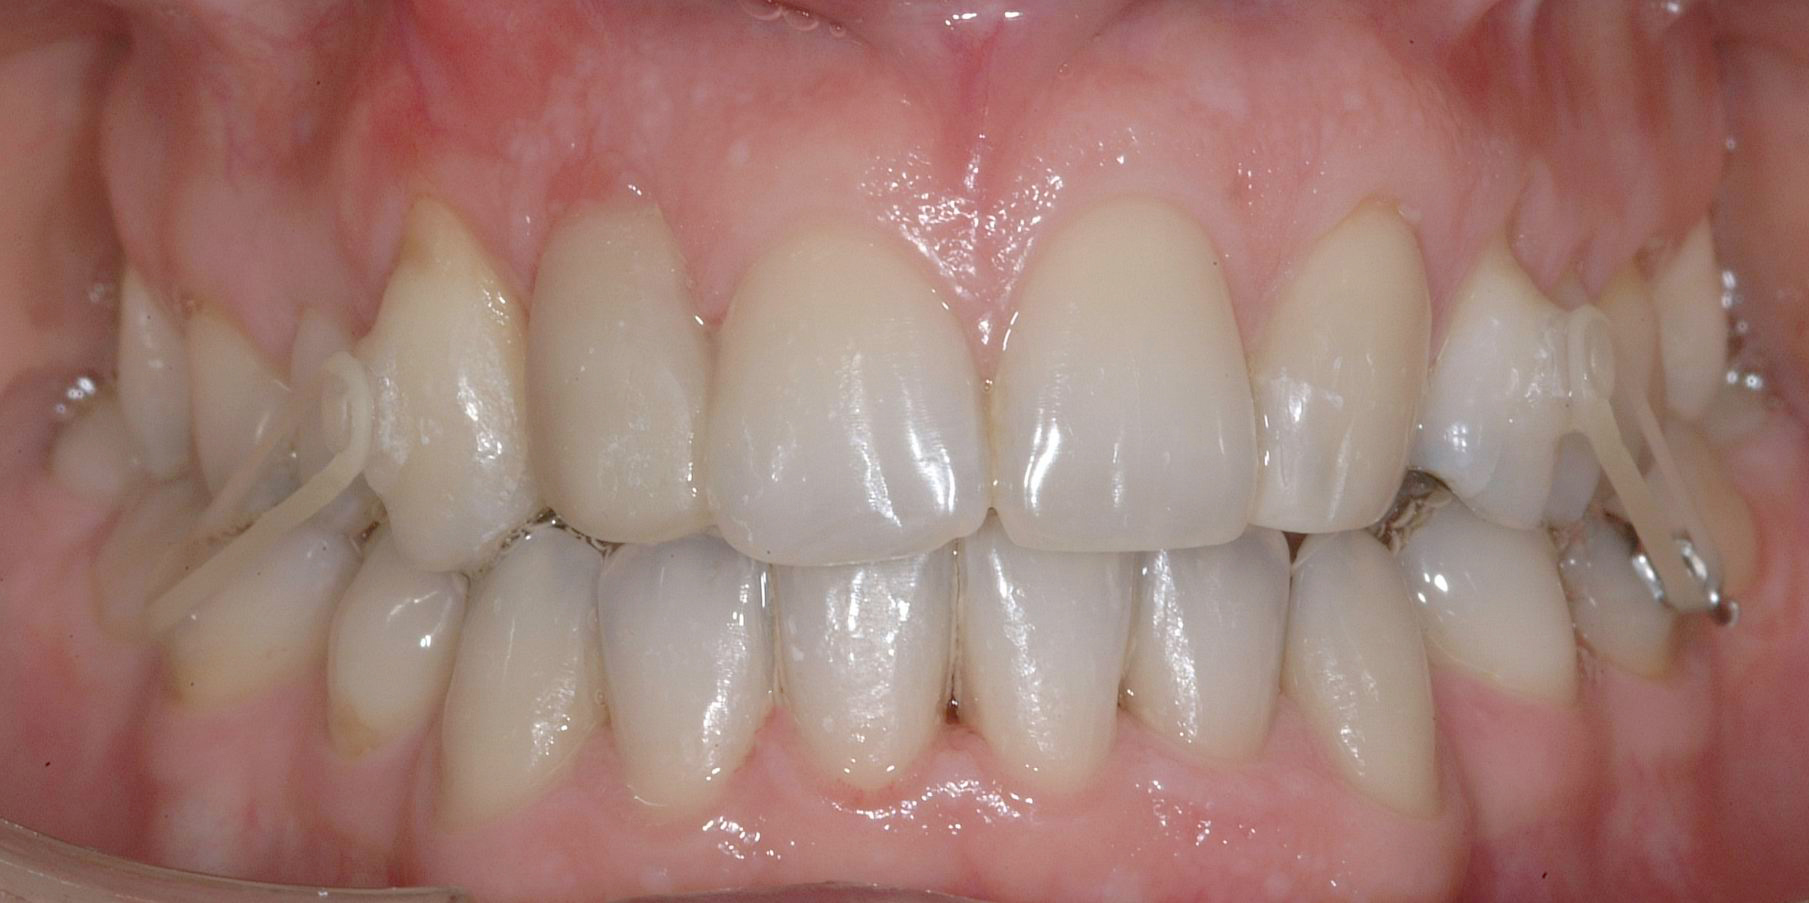

Al termine del trattamento ortodontico, che ha richiesto 24 mesi di terapia, è stata applicata una contenzione fissa3 all’arcata inferiore mediante filo multi-intrecciato coassiale .0195” esteso da 4.4 a 3.5 al fine non solo di stabilizzare il risultato sia sul piano orizzontale sia verticale, ma soprattutto per prevenire adeguatamente l’affollamento dentale terziario (Figure 9a-e).

All’arcata superiore è stato mantenuto il pontic in composito in sede 1.2, poiché la paziente, per esigenze personali, aveva preferito rimandare a un tempo successivo la sostituzione implantare di 1.2 agenesico, così come la coronoplastica definitiva di 2.3.

Dopo tre anni dal termine del trattamento ortodontico, la paziente ha richiesto di finalizzare il suo caso; è dunque stata effettuata la sostituzione implanto-protesica dell’elemento 1.2, senza necessità di ulteriori rifiniture ortodontiche, avendo mantenuto, grazie al pontic in composito, un ottimo parallelismo radicolare tra 1.1 e 1.3.

È stata eseguita contestuale terapia rigenerativa, per ottimizzare qualità e quantità dei tessuti nel sito implantare. Come si rileva dalle immagini di follow up, dopo la fase implanto-protesica superiore, è stata applicata anche una parziale contenzione fissa tra gli incisivi centrali superiori e il risultato ortodontico si è mantenuto stabile nel tempo (Figure 10 a-e).